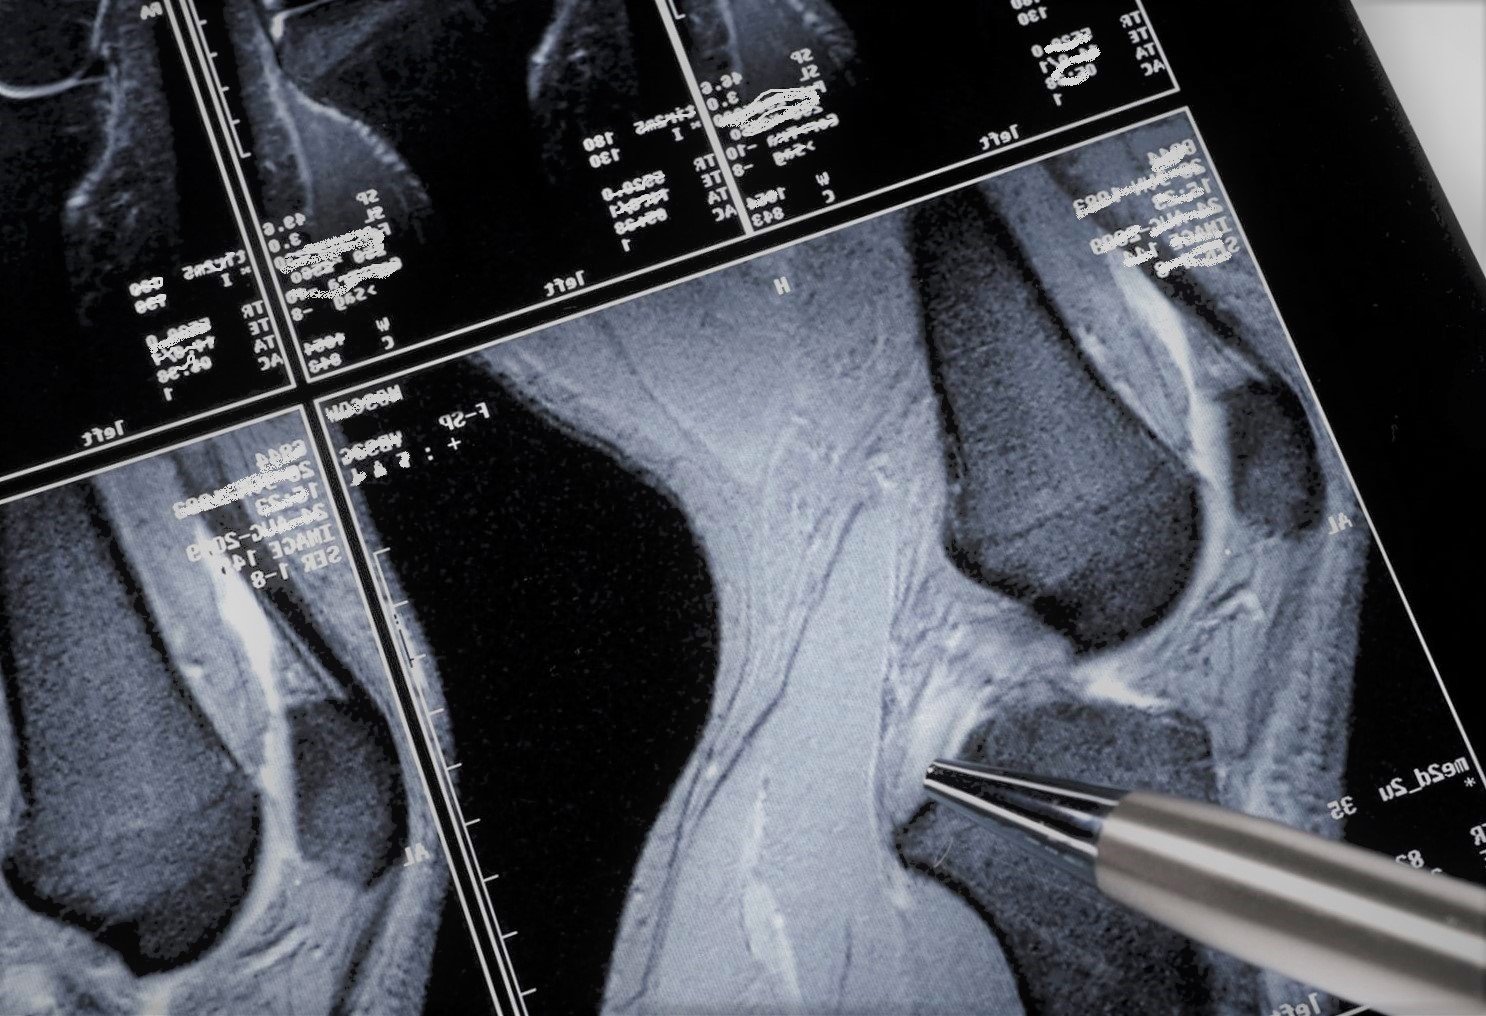

El ilustre tomó asiento, abrió la

carpeta con las pruebas que tres semanas antes me había encargado, miró arriba

y abajo, golpe de ratón por aquí, golpe de ratón por allá mientras el interior

de mi rodilla aparecía en la pantalla de ordenador más grande que he visto

nunca.